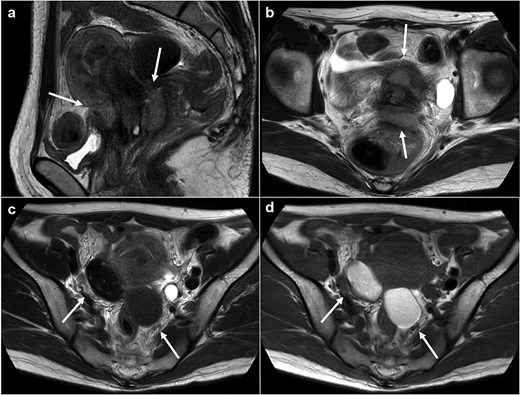

Magnetic resonance imaging revealed masses on the anterior uterine wall, as well as on the posterior uterine wall (Fig. 1a and b). Endometrial cysts were confirmed in the Douglas pouch (Fig. 1c and d). Computed tomography revealed left hydroureter and hydronephrosis, and no distant or lymph node metastases were observed. A Tc99m-diethylenetriaminepentaacetic acid renal renogram showed that the left kidney was nonfunctional. 18F-fluorodeoxyglucose (FDG)-positron emission tomography and computed tomography showed that abnormal FDG accumulation was observed only in the pelvis (Fig. 2). At first, no lesions were found on the uterine cervix or vaginal walls, and the cervical and endometrial cytology were negative. However, as time passed, the tumor emerged on the posterior vaginal fornix and was histologically diagnosed as high-grade endometrioid carcinoma (Fig. 3).

Magnetic resonance images. (a) Sagittal T2 weighted image. (b) Axial T2 weighted image. (c) Axial T1 weighed image. (d) Axial T2 weighed image. Tumors are observed at either the anterior or posterior portion of the urine cervix (a, b: arrows). Ovarian endometriosis is observed in both ovaries (c, d: arrows). Walls of the cysts are smooth.